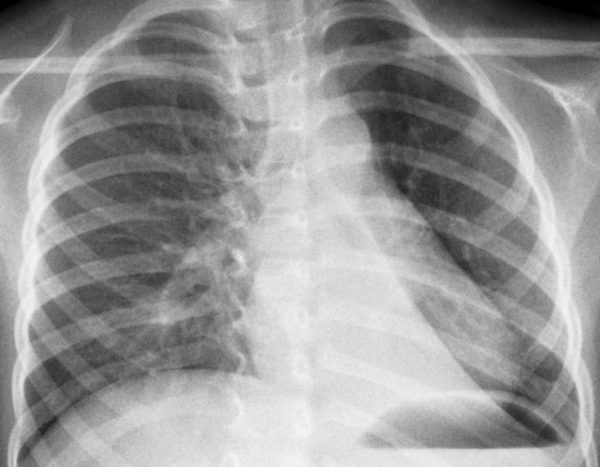

Одним з провідних діагностичних досліджень є рентгенографія органів грудної клітки. На знімку можна побачити розширення легеневого кореня, вогнища в зоні проекції коренів легень.

Щоб поставити точний діагноз прикореневій форми пневмонії, проводяться рентгенологічні обстеження. Ознаки її на знімках виражаються маленькими, світлими, округлими ділянками на легеневої тканини. Пройшовши рентген, його слід показати лікарю та отримати консультацію.